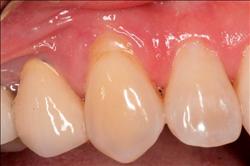

Cosmetic Soft Tissue Grafting

In addition to the functional problems previously mentioned, receding gums can look unsightly.

Longer looking teeth and exposed tooth roots give an "old" appearance to your smile. Some people cover their mouths when they smile for this very reason.

Cosmetic Soft Tissue Grafting can add a new youthful appearance to your smile. In your initial consultation with Dr. Hoidal, he will thoroughly explain what can be achieved in your particular case.